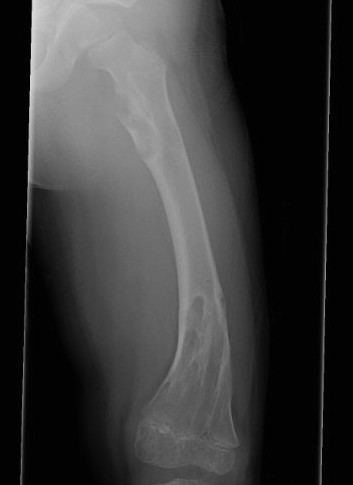

Femur / tibia / humerus

Growth disturbance

- leg length discrepancy

- bowing

Leg length discrepancy

Popkov et al Orthop Traumatol Surg Res 2010

- limb lengthening in Olliers

- external fixator versus external fixator + IM nail

- use of nail reduced external fixator time, complications, and fractures

Hosny et al J Pediatr Orthop B 2023

- 13 patients with LLD and angular deformity

- intralesional osteotomy and distraction osteotomy

- in conjunction with guided growth

- good correction and bone regeneration